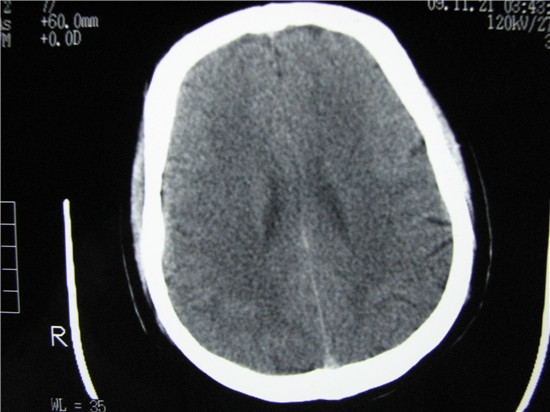

标题: CT23231:男 32岁 车祸伤,鼻腔内出血明显。 [打印本页]

标题: CT23231:男 32岁 车祸伤,鼻腔内出血明显。